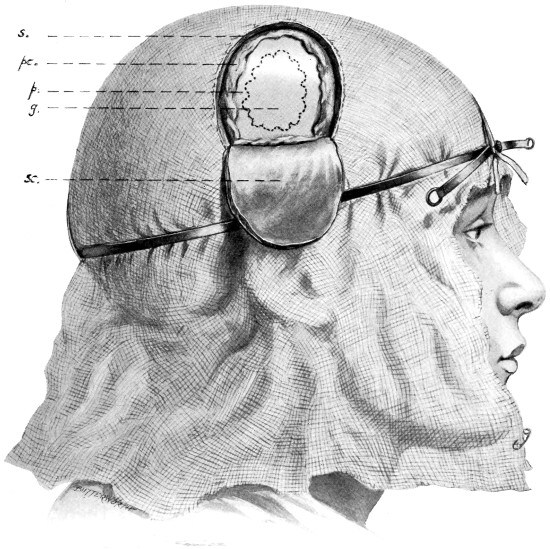

Fig. 4. The Scalp-tourniquet. Front View.

Fig. 5. The Scalp-tourniquet. Back View.

I found Cushing’s tourniquet rather inconvenient in its application, and, after various modifications, am accustomed to use the one depicted in the illustration. It consists of two flat metal bands connected posteriorly by a strong rubber connecting link, the two bands passing in front through a metal fixation piece possessing a screw which, when tightened up, allows of the maintenance of the desired pressure. The median tape, previously mentioned, helps to keep the tourniquet in position.

The tourniquet is applied as follows: the whole head is enveloped in gauze—two or three layers thick, and cut to the size and shape of a large handkerchief. The tourniquet is slipped over the head,[16] as low down as possible, and then tightened up. The median tape, having a loop behind through which the tourniquet passes, is laid in the middle line and tied round the screw on the fixation piece.

The gauze should then be moistened with saline solution or some mild antiseptic, so that it clings tightly to the underlying scalp and becomes sufficiently translucent to allow of the recognition of any underlying landmarks that may have been previously mapped out with the scalpel, iodine, silver nitrate, or aniline pencil.

The scalp-flap is then framed by incisions carried down to the bone, through gauze and scalp, in one sweep. The flap is turned down and covered with gauze. By the adoption of this method hæmorrhage from scalp-vessels is efficiently controlled and the risk of wound infection is reduced to a minimum.